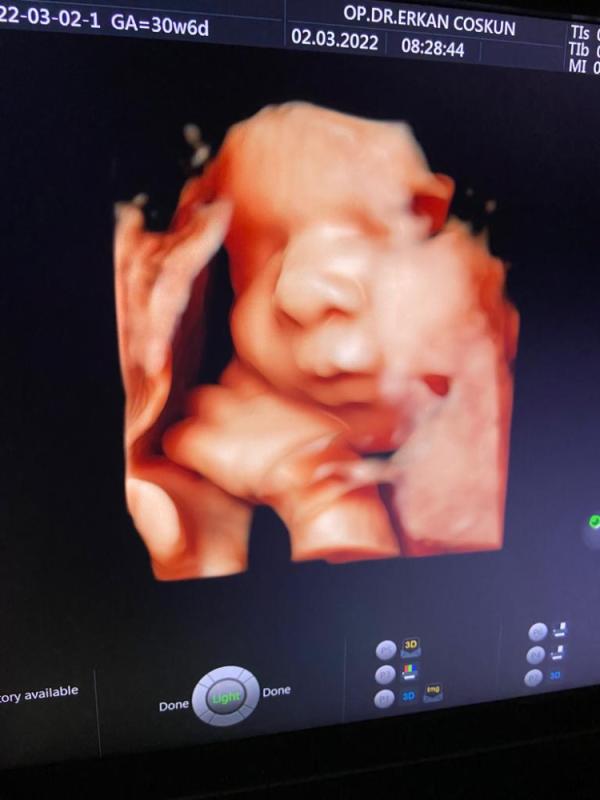

Detaylı(ayrıntılı)ultrason

Detaylı ultrason nedir?Detaylı ultrason nerede çekilirBundan 15-20 yıl öncesine kadar annelerin çoğu bebeklerini kucakladıkları ana kadar sağlık d...